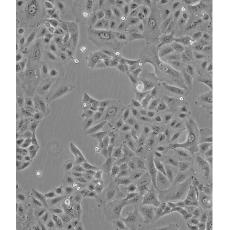

A549/DDP

中文名稱 人肺腺癌耐順鉑株

生長特性 adherent

形態特征 epithelial